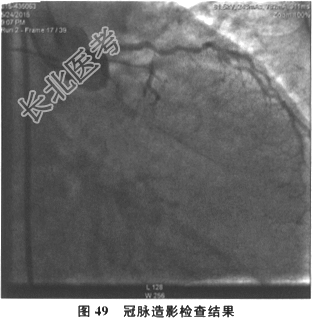

- 多项选择题7.[提示]患者数天后,行冠状动脉造影检查: 前降支近段70%狭窄,近中段次全闭塞, 间隔支可见左向右Ⅱ级侧支循环供血至右冠后降支。回旋支近段闭塞,右冠状动脉近中段闭塞。结果如图48、图49及图50所示。